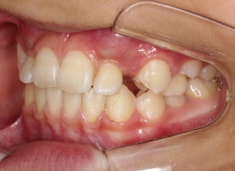

治療前

FX(フェイシャルアキシス)は85度なので東洋人の平均値に近く、下顎が前方に過剰成長するリスクは強くはありません。

しかしやはり上顎は劣成長で、下顎が優位な状態ではあります。